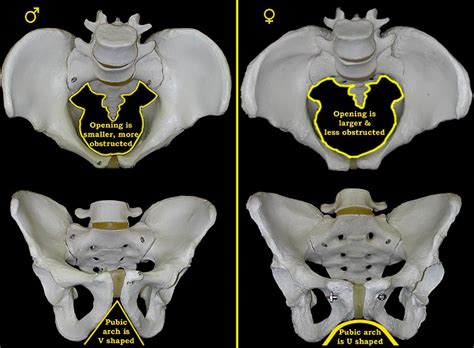

Male Pelvis Vs Female Pelvis, Differences Between the Male and Female Pelvis (With images) : Male pelvis has a longer and narrower sacrum whereas female pelvis has wider, shorter, and less curved sacrum.. The distance between the ischium bones is small in males. What are the names of the female pelvis? Which pelvis in the illustration above is the male pelvis? 15 major differences (with diagram) the pelvis. • female pelvis has a shallow pelvic cavity, and it is wider than male pelvis.

Vleeming Seminar - Take Home Tips | Nottingham, NTT ... from cdn.vortala.com What is the difference between male and female pelvis? This causes the sides of the. Which pelvis in the illustration above is the male pelvis? More images for male pelvis vs female pelvis » In this video you will learn about the following differences between male and female pelvis.structure1.a male pelvis is smaller and narrower while a fema. The female pelvis is larger and broader than the male pelvis, which is taller (owing to a higher iliac crest), narrower,. Females have a subpubic angle that is wider (larger, more obtuse) than males, measuring around 80 degrees or more. Male pelvis has a longer and narrower sacrum whereas female pelvis has wider, shorter, and less curved sacrum.

What are the names of the female pelvis? • the bones of male pelvis are heavier, thicker and stronger while the bones of female pelvis are lighter and less dense. • female pelvis has a shallow pelvic cavity, and it is wider than male pelvis. Male pelvis has a longer and narrower sacrum whereas female pelvis has wider, shorter, and less curved sacrum. The pelvic brim (also called pelvic inlet) is. What is a skeleton pelvis? The distance between the ischium bones is small in males. 15 major differences (with diagram) the pelvis. Aug 13, 2020 · there are several diagnostic criteria for differentiating a male from a female pelvis: In this video you will learn about the following differences between male and female pelvis.structure1.a male pelvis is smaller and narrower while a fema. The female pelvis is larger and broader than the male pelvis, which is taller (owing to a higher iliac crest), narrower,. Females have a subpubic angle that is wider (larger, more obtuse) than males, measuring around 80 degrees or more. More images for male pelvis vs female pelvis »

Anatomy of the Pelvis | Proko from www.proko.com The female pelvis is larger and broader than the male pelvis, which is taller (owing to a higher iliac crest), narrower,. What is a skeleton pelvis? Aug 13, 2020 · there are several diagnostic criteria for differentiating a male from a female pelvis: What are bones in the pelvic area? • the bones of male pelvis are heavier, thicker and stronger while the bones of female pelvis are lighter and less dense. Females have a subpubic angle that is wider (larger, more obtuse) than males, measuring around 80 degrees or more. Male pelvis has a longer and narrower sacrum whereas female pelvis has wider, shorter, and less curved sacrum. Which pelvis in the illustration above is the male pelvis?

Females have a subpubic angle that is wider (larger, more obtuse) than males, measuring around 80 degrees or more.

This causes the sides of the. In this video you will learn about the following differences between male and female pelvis.structure1.a male pelvis is smaller and narrower while a fema. • the bones of male pelvis are heavier, thicker and stronger while the bones of female pelvis are lighter and less dense. Aug 13, 2020 · there are several diagnostic criteria for differentiating a male from a female pelvis: What is the difference between male and female pelvis? The pelvic brim (also called pelvic inlet) is. What are the names of the female pelvis? Which pelvis in the illustration above is the male pelvis? What is a skeleton pelvis? • female pelvis has a shallow pelvic cavity, and it is wider than male pelvis. 15 major differences (with diagram) the pelvis. The female pelvis is larger and broader than the male pelvis, which is taller (owing to a higher iliac crest), narrower,. Male pelvis has a longer and narrower sacrum whereas female pelvis has wider, shorter, and less curved sacrum.